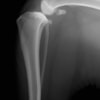

術前側面像

術後側面像